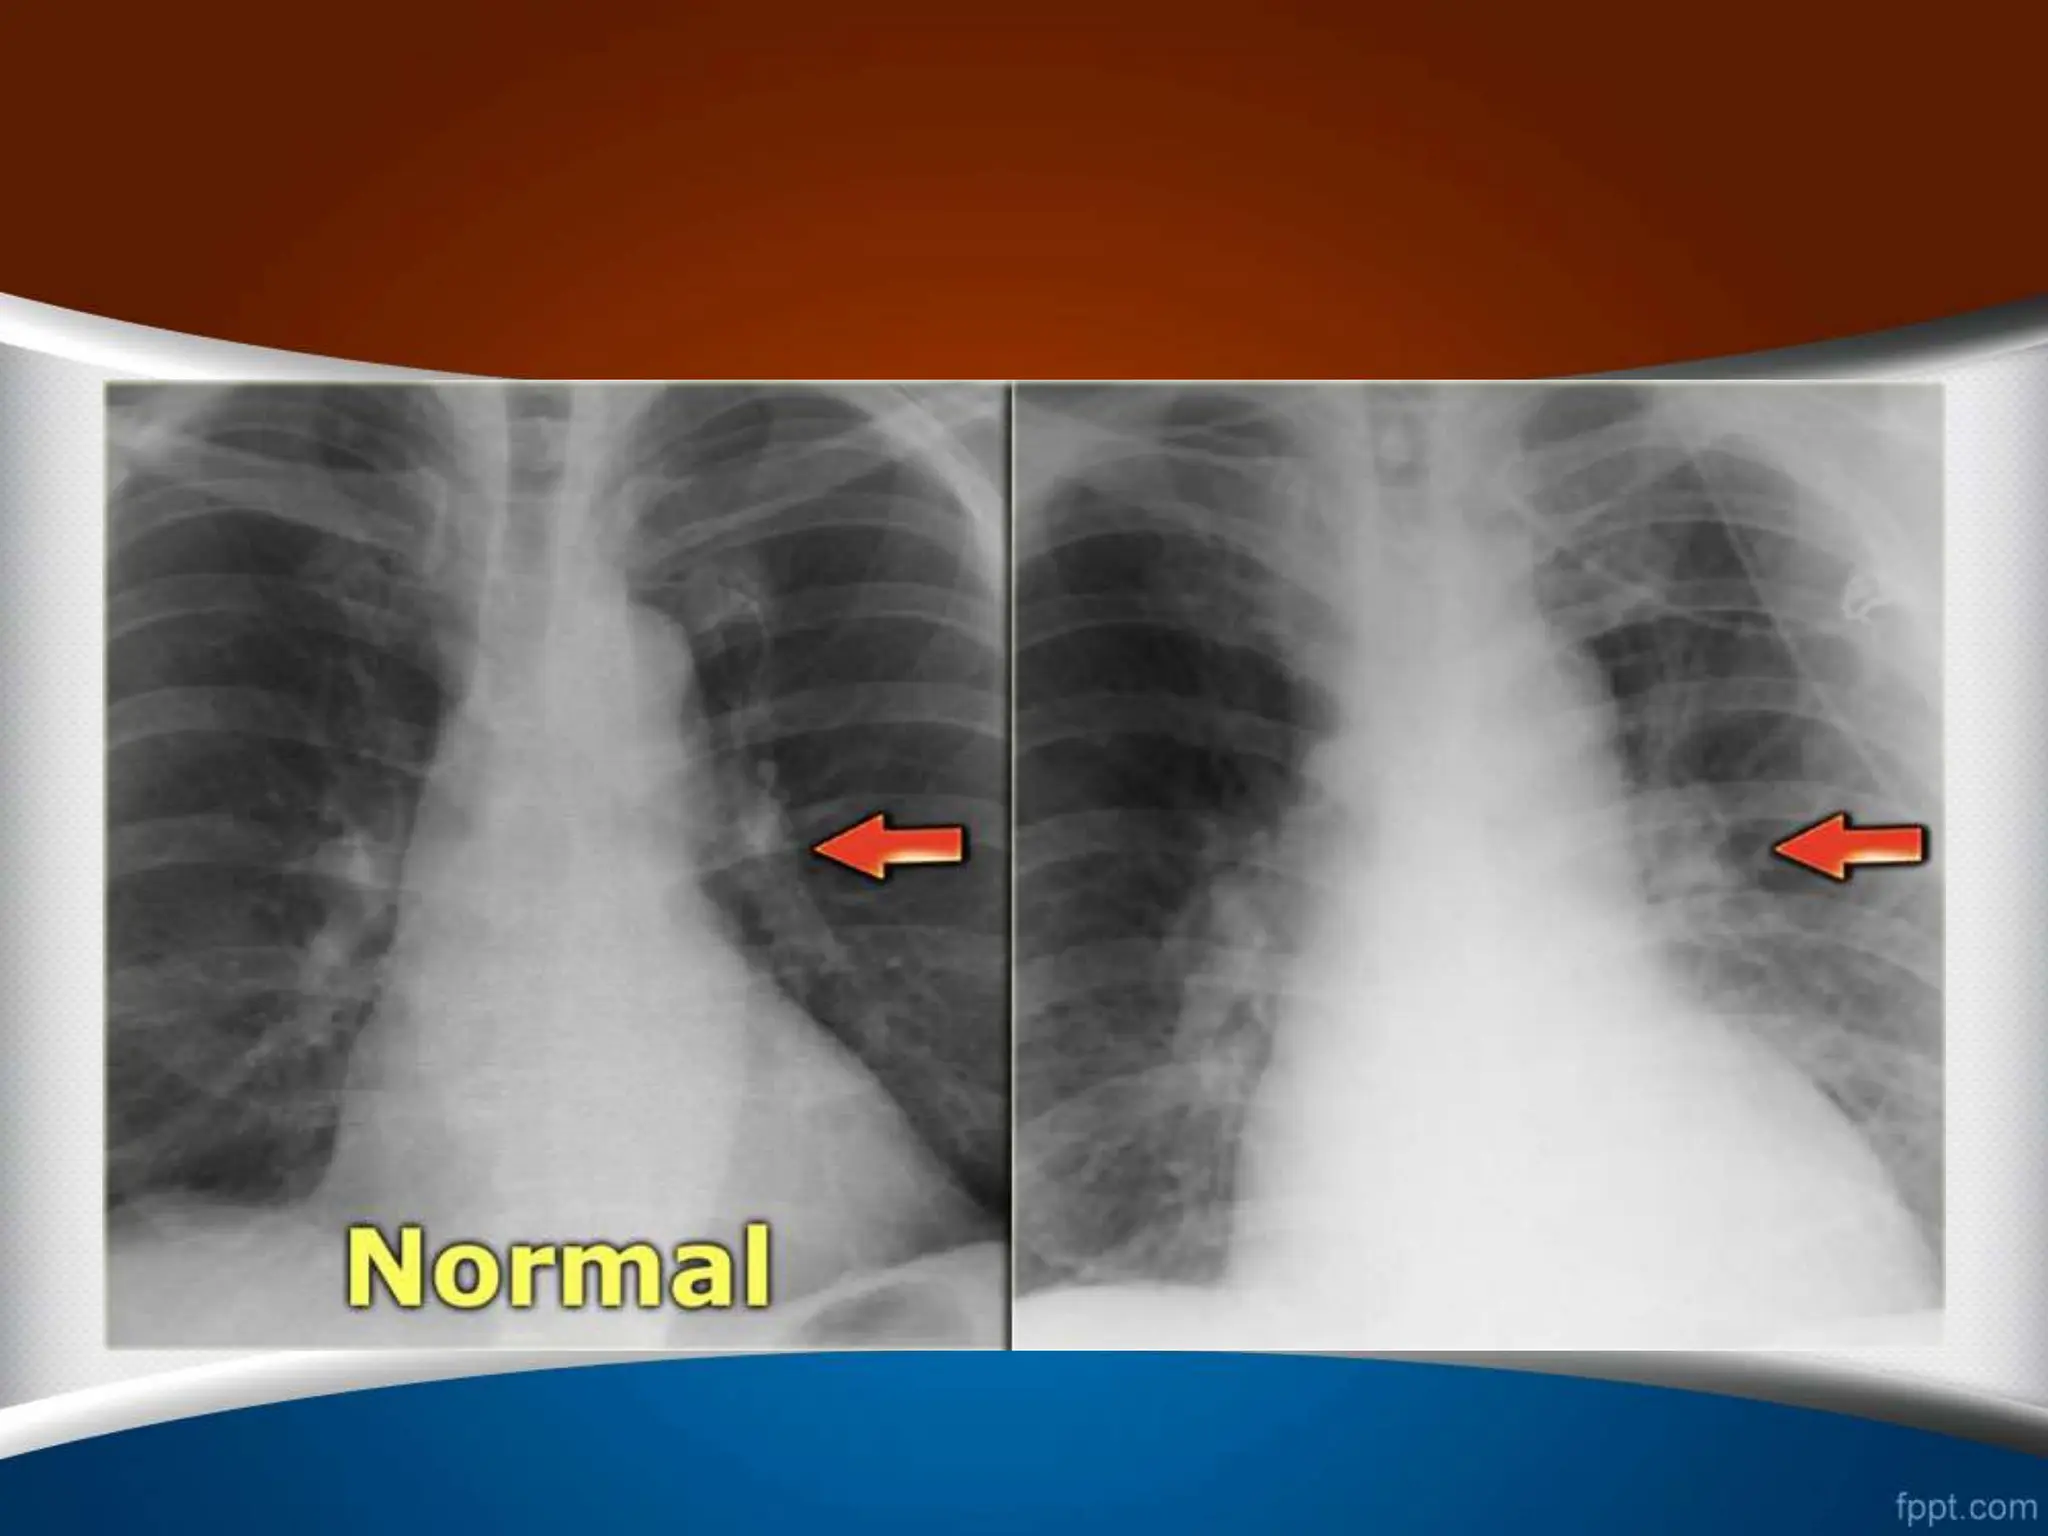

‫چرخش‬ –Rotation

•

‫حاشیه‬ ‫و‬ ‫کند‬ ‫پیدا‬ ‫تغییر‬ ‫قلب‬ ‫کلی‬ ‫شکل‬

‫نامنظم‬ ‫را‬ ‫قلب‬ ‫های‬

‫کند‬

.

(Abnormal configuration)

‫دهد‬ ‫قرار‬ ‫تأثیر‬ ‫تحت‬ ‫را‬ ‫ریه‬ ‫عروقی‬ ‫طرح‬

‫طرح‬ ‫که‬ ‫طور‬ ‫به‬

‫نزدیک‬ ‫اشعه‬ ‫به‬ ‫که‬ ‫سمتی‬ ‫در‬ ‫عروقی‬

‫در‬ ‫و‬ ‫کمتر‬ ‫است‬ ‫تر‬

‫شود‬ ‫دیده‬ ‫بیشتر‬ ‫است‬ ‫دورتر‬ ‫اشعه‬ ‫از‬ ‫که‬ ‫سمتی‬

‫زوایای‬ ‫شدن‬ ‫محو‬ ‫به‬ ‫منجر‬ ‫است‬ ‫ممکن‬ ‫بیمار‬ ‫چرخش‬

‫خانم‬ ‫در‬ ً‫ا‬‫مخصوص‬ ‫کوستوفرنیک‬

‫ها‬

(

‫افزایش‬ ‫خاطر‬ ‫به‬

‫پستان‬ ‫بافت‬ ‫دانسیته‬

)

‫اشتبا‬ ‫به‬ ‫است‬ ‫ممکن‬ ‫که‬ ‫شود‬

‫مطرح‬ ‫ه‬

‫یا‬ ‫و‬ ‫مایع‬ ‫تجمع‬ ‫جمله‬ ‫از‬ ‫پاتولوژی‬ ‫از‬ ‫مواردی‬ ‫شدن‬

‫سازد‬ ‫مطرح‬ ‫را‬ ‫منطقه‬ ‫این‬ ‫فضاگیر‬ ‫ضایعات‬

‫چپ‬ ‫به‬ ‫چرخش‬

.1

‫بزرگتر‬ ‫قلب‬

.2

‫خونتر‬ ‫کم‬ ‫چپ‬ ‫ریه‬ ‫فیلد‬

‫راست‬ ‫به‬ ‫چرخش‬

‫کوچکتر‬ ‫قلب‬

‫خونتر‬ ‫کم‬ ‫راست‬ ‫ریه‬ ‫فیلد‬

‫چپ‬ ‫به‬ ‫چرخش‬ ‫راست‬ ‫به‬ ‫چرخش‬

‫چرخش‬ –Rotation • ‫حاشیه‬ ‫و‬‫کند‬ ‫پیدا‬ ‫تغییر‬ ‫قلب‬ ‫کلی‬ ‫شکل‬ ‫نامنظم‬ ‫را‬ ‫قلب‬ ‫های‬ ‫کند‬ . (Abnormal configuration) • ‫دهد‬ ‫قرار‬ ‫تأثیر‬ ‫تحت‬ ‫را‬ ‫ریه‬ ‫عروقی‬ ‫طرح‬ . ‫طرح‬ ‫که‬ ‫طور‬ ‫به‬ ‫نزدیک‬ ‫اشعه‬ ‫به‬ ‫که‬ ‫سمتی‬ ‫در‬ ‫عروقی‬ ‫در‬ ‫و‬ ‫کمتر‬ ‫است‬ ‫تر‬ ‫شود‬ ‫دیده‬ ‫بیشتر‬ ‫است‬ ‫دورتر‬ ‫اشعه‬ ‫از‬ ‫که‬ ‫سمتی‬ . • ‫زوایای‬ ‫شدن‬ ‫محو‬ ‫به‬ ‫منجر‬ ‫است‬ ‫ممکن‬ ‫بیمار‬ ‫چرخش‬ ‫خانم‬ ‫در‬ ً‫ا‬‫مخصوص‬ ‫کوستوفرنیک‬ ‫ها‬ ( ‫افزایش‬ ‫خاطر‬ ‫به‬ ‫پستان‬ ‫بافت‬ ‫دانسیته‬ ) ‫اشتبا‬ ‫به‬ ‫است‬ ‫ممکن‬ ‫که‬ ‫شود‬ ‫مطرح‬ ‫ه‬ ‫یا‬ ‫و‬ ‫مایع‬ ‫تجمع‬ ‫جمله‬ ‫از‬ ‫پاتولوژی‬ ‫از‬ ‫مواردی‬ ‫شدن‬ ‫سازد‬ ‫مطرح‬ ‫را‬ ‫منطقه‬ ‫این‬ ‫فضاگیر‬ ‫ضایعات‬ .

‫چپ‬ ‫به‬ ‫چرخش‬ .1 ‫بزرگتر‬‫قلب‬ .2 ‫خونتر‬ ‫کم‬ ‫چپ‬ ‫ریه‬ ‫فیلد‬ ‫راست‬ ‫به‬ ‫چرخش‬ .1 ‫کوچکتر‬ ‫قلب‬ .2 ‫خونتر‬ ‫کم‬ ‫راست‬ ‫ریه‬ ‫فیلد‬